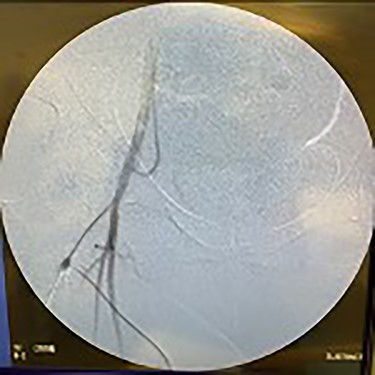

Fluoroscopy of bilateral iliac arteries showing significant arterial disease.